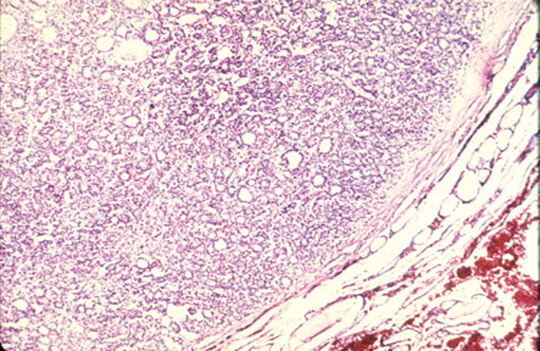

- Hyperthyroidism: microscopic section of the thyroid gland reveals

hyperplasia. Most follicles are lined by hyperplastic epithelium which forms papillary structure. Colloid is decreased is most follicles.